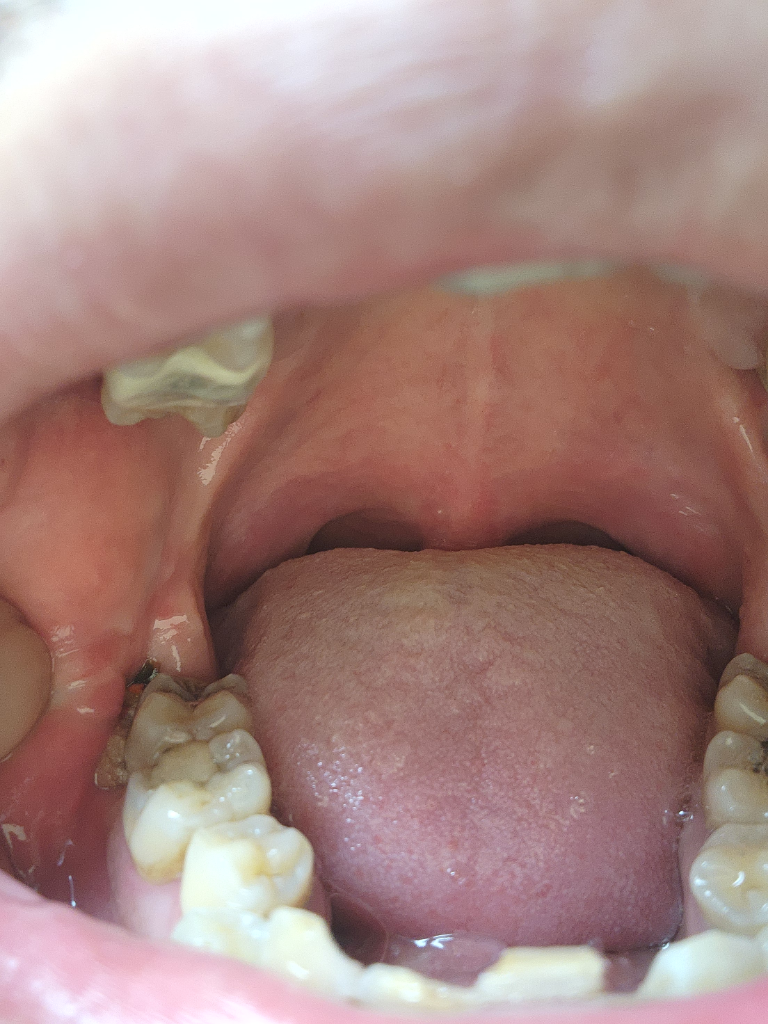

왼쪽 아래 매복사랑니 발치하엿는데요 2주가 지난 시점 입니다 저기 노란색은 염증 인가요?그뒤에 검은색은 드라이소켓인지 구멍이 잇는데 무슨 문제라도 생긴걸까요

• 1번 째 사진

사진으로는 정확한 판단이 힘들어 보입니다. 특별히 불편감이 없다면 큰 문제가 없을 가능성이 높으면 발치한 부위는 자극을 하지 않는 것이 치유에 도움이 됩니다

사랑니 발치를 하고나서 잇몸이 치유되는과정중에 자연스럽게 생기는 현상이니 너무 걱정하지 않으셔도 될것같습니다.

상처부위가 아물면서 혈병이 생긴것으로 보이며 크게 문제가 되어 보이는 부분은 없기에 걱정하지 않아도 됩니다. 염증이 덧나지 않게 소독용 헥사메딘 가글로 가글하고, 양치를 꼼꼼히하여 음식물 찌꺼기가 남지 않도록 관리하길 권합니다.

드라이소켓은 발치 후 3~5일 후 나타나는 극심한 통증과 악취가 특징인 염증상태를 의미합니다

현재 그러한 증상은 없다면 드라이소켓으로 단정지을 수 없고 다만 치유가 조금 느린 상태로 보여집니다

해당부위 음식물끼어있지 않도록 제때 잘 제거해주어야 잇몸치유가 지연되지 않습니다